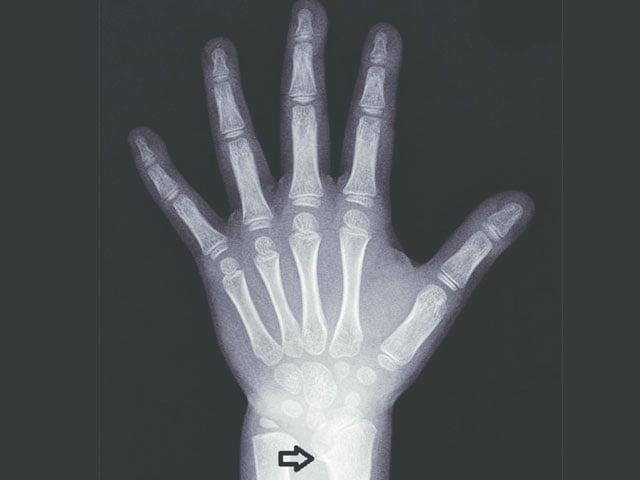

Kemik yaşı araştırması, doktorların bir çocuğun iskelet sisteminin olgunluğunu tahmin etmesine yardımcı olur. Genellikle sol bileğin, elin ve parmakların tek bir röntgeni çekilerek yapılır. Az miktarda radyasyon kullanan güvenli ve ağrısız bir işlemdir. Röntgen görüntüsündeki kemikler, aynı cinsiyet ve yaştaki çok sayıda diğer çocuktan alınan verilere dayanan standart bir kemik gelişimi atlasında X ışını görüntüleriyle karşılaştırılır.

Kemik yaşı yıl olarak ölçülür. Bir çocuğun parmakları ve el bileğindekiler gibi kemiklerinin her iki ucunda büyüme plakaları adı verilen “büyüme bölgeleri” bulunur. Bu plakalar, kemiklerin uzunlamasına büyümesinden sorumlu özel hücrelerden oluşur. Büyüme plakalarının bir röntgende fark edilmesi kolaydır, çünkü daha yumuşaktırlar ve daha az mineral içerirler, bu da onları bir röntgen görüntüsünde kemiğin geri kalanından daha koyu gösterir.

Çocuklar büyüdükçe, büyüme plakalarının X-ışını görüntülerinde görünümü değişir ve incelir, sonunda kaybolur (buna “kapalı büyüme plakaları” denir). Her yaşta farklı göründükleri için, doktor kemiklerin ve büyüme plakalarının görünümüne göre bir kemik yaşı belirleyebilir.

Bir çocuğun kemik yaşı (iskelet yaşı olarak da adlandırılır), atlastaki standart X-ışını görüntülerinden hangisinin çocuğun kemiklerinin röntgen üzerindeki görünümüne en yakın eşleştiğini belirleyerek belirlenir. Bir çocuğun kemik yaşı ile kronolojik yaşı arasındaki fark, bir büyüme sorununa işaret edebilir. Ancak bu tür farklılıklar her zaman bir sorun olduğu anlamına gelmez, çünkü mükemmel sağlıklı çocuklar kronolojik yaşlarından farklı kemik yaşlarına sahip olabilirler.